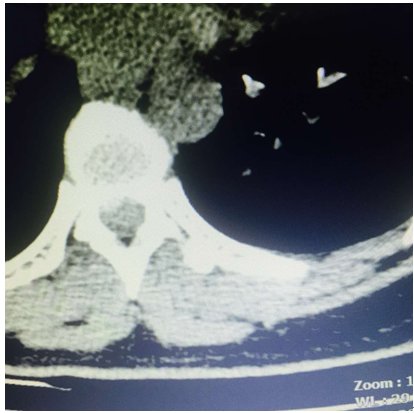

术前CT

(术前CT